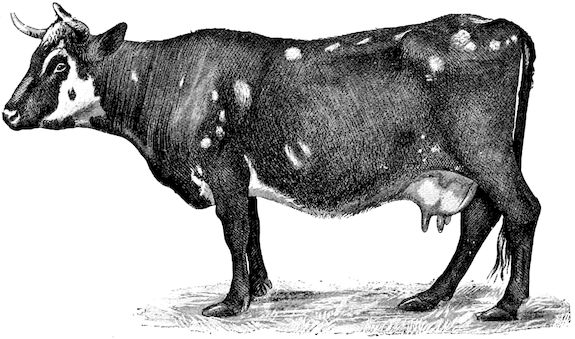

Fig. 3.—Pig suffering from osseous cachexia (fourth stage).

3. The third phase is characterised by fractures, and it is this peculiarity of the disease which has procured for it the names of fragilitas ossium, and osteoclastia. These fractures may affect any portion of the skeleton. Animals so suffering sometimes break a leg whilst trotting or the pelvis in simply jumping over a ditch; a collision with a fixed object like the jamb of the stable door, or a fall on the ground, may result in the fracture of one or several ribs.

Such shocks would be of no importance to a healthy animal, but to one suffering from osseous cachexia, any violence, or even the slightest muscular effort may be followed by fracture of the gravest character, involving even the vertebral column. In cows the pelvis, femur, and tibia are most frequently injured.

In horses, particularly in riding horses, fractures are commonest in the region of the forearm, cannon bone, and anterior phalanges. So extremely fragile are the bones at this stage that the horse represented herewith broke twelve ribs at one time by simply falling on its side. It is interesting to note that such fractures are never accompanied by any extensive bleeding. They have little tendency to repair, no real callus formation occurs, and on post-mortem examination one often finds the ends unconnected by temporary callus, worn, and rounded by reciprocal friction.

At this stage but under other circumstances, the animals show great reluctance to rise, remaining down for twelve to twenty-four hours without shifting their position. If forced to get up, they stand as though fixed in one position, the respiration and circulation become rapid, and they soon grow tired and fall.

114. The fourth phase, or period of osteomalacia, i.e. softening of the bones, is also the last. It is rarely seen in large animals like horses and oxen, because accidents so often accompany the preceding stages and necessitate slaughter; but it is common in goats and pigs.

In this phase the bones become elastic, soft and depressible, yielding to the pressure of the operator’s fingers.